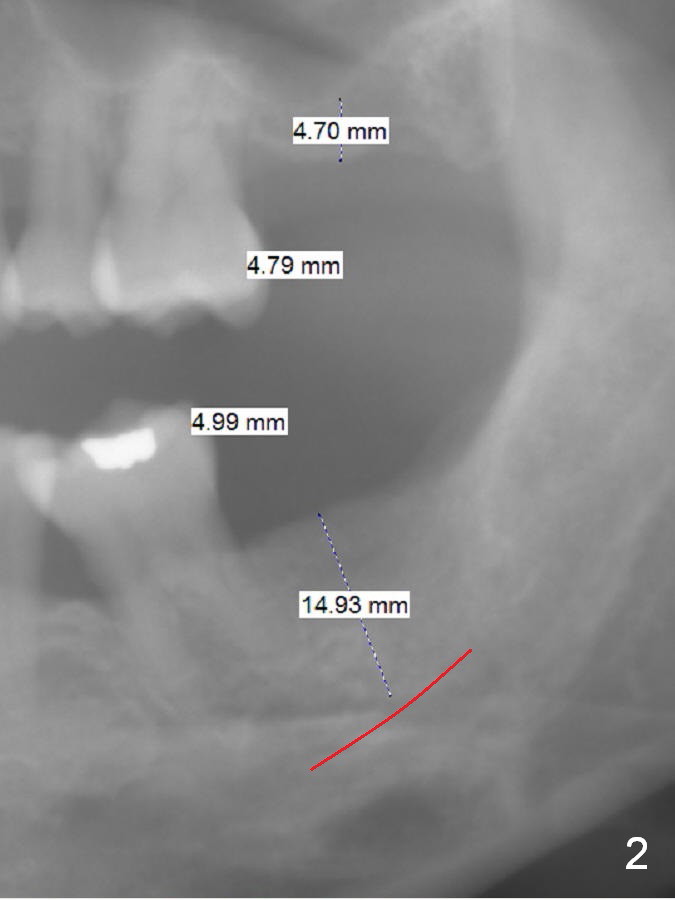

Implants Keep Posterior Vertical Height A 32-year-old woman is concerned about her upper anterior tooth flaring (Fig.1). She is eager for periodontal treatment. She masticates on the right side. The teeth #15 and 18 were extracted ~ 1 year ago. To lessen anterior flaring (take photos when she returns), implants are going to be placed at these sites (Fig.2,3). IBS and Magic Sinus Lift Kits will be used for #15. Magic Split gains access for 5 mm deep (gingival level), followed by ME 3 mm and next ME for 5 mm and Sinus lifter for 9 mm (bone level 7 mm, CMC). Or use the 4.3 mm drill from Magic Sinus Lift Kit for 5 mm, followed by Sinus Lifter for 9 mm. Insert PRF plugs into the sinus, followed by allograft (.5-1.0 mm) with Osteogen. If implant stability is low, place a healing abutment or screw. For #18 implant placement, palpate the ridge to determine the width. Trim the ridge if it is pointed. Also use Magic split for access and bone density testing. Either BEB or PBR will be adopted. The patient is interested in orthodontic treatment. Take Alginate impression and facial photos. Return to Upper Lower Molar Immediate Implant, IBS Xin Wei, DDS, PhD, MS 1st edition 11/15/2016, last revision 01/22/2017 |